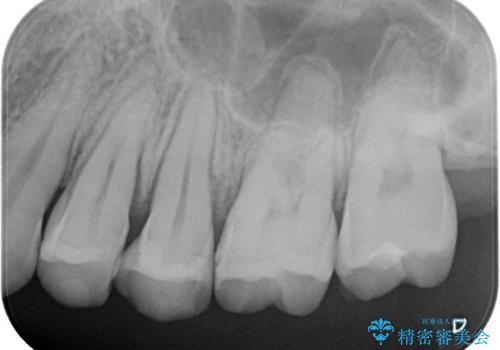

奥歯の着色が気になる セラミック治療

- 矯正終了後検査を行ったところ、以前詰めていたプラスチックの材料が着色し劣化していたこともあり、検査したところ虫歯になっていたところがあったため治療を進めることとなった。

劣化していたプラスチックをとって、虫歯をとり、形を作って、型取りをして、精度の高い詰め物(インレー)をしています。